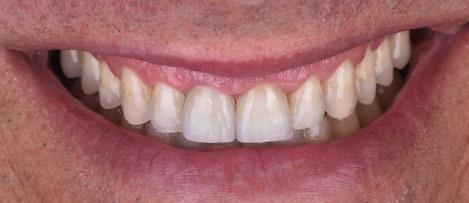

Figura 11. Resultado clínico a 12 meses de seguimiento. a) situación en oclusión. Vista frontal/vestibular. b) vista oclusal del quinto sextante. c) vista frontal/ vestibular del quinto sextante; d) vista de perfil/ lateral del quinto sextante.

En un seguimiento a medio plazo, se puede observar un mantenimiento adecuado de los resultados en términos de salud periodontal, cobertura radicular, aumento de encía queratinizada y de profundidad de vestíbulo.